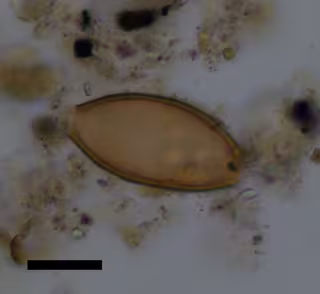

Restos del parásito descubierto

Los investigadores de la Universidad de Cambridge, en Reino Unido, Evilena Anastasiou y Piers Mitchell utilizaron microscopía para estudiar el suelo formado por heces descompuestas recuperadas de la superficie de huesos pélvicos de esqueletos enterrados en el Neolítico (cuarto milenio aC), la Edad de Bronce (segundo milenio aC) y los periodos romanos (del año 146 aC al 330 dC).

El equipo de Cambridge trabajó en este proyecto con Anastasia Papathanasiou y Lynne Schepartz --con sede en Atenas-- que son expertas en arqueología y antropología de la antigua Grecia. Los investigadores descubrieron que estaban presentes los huevos de dos especies de gusanos parásitos (helmintos): tricocéfalos ('Trichuris trichiura') y lombrices intestinales ('Ascaris lumbricoides'). El tricocéfalo estaba presente desde el Neolítico, y lombriz, a partir de la Edad del Bronce.